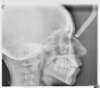

Béance traitée par gouttières

Début du traitement